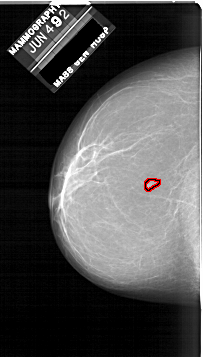

A_1860_1.LEFT_MLO

LEFT_MLO LINES 6871 PIXELS_PER_LINE 3586 BITS_PER_PIXEL 12 RESOLUTION 43.5 OVERLAY

FILE: A_1860_1.LEFT_MLO.OVERLAY

TOTAL_ABNORMALITIES 1

ABNORMALITY 1

LESION_TYPE MASS SHAPE IRREGULAR MARGINS ILL_DEFINED

ASSESSMENT 4

SUBTLETY 3

PATHOLOGY BENIGN

TOTAL_OUTLINES 1

BOUNDARY